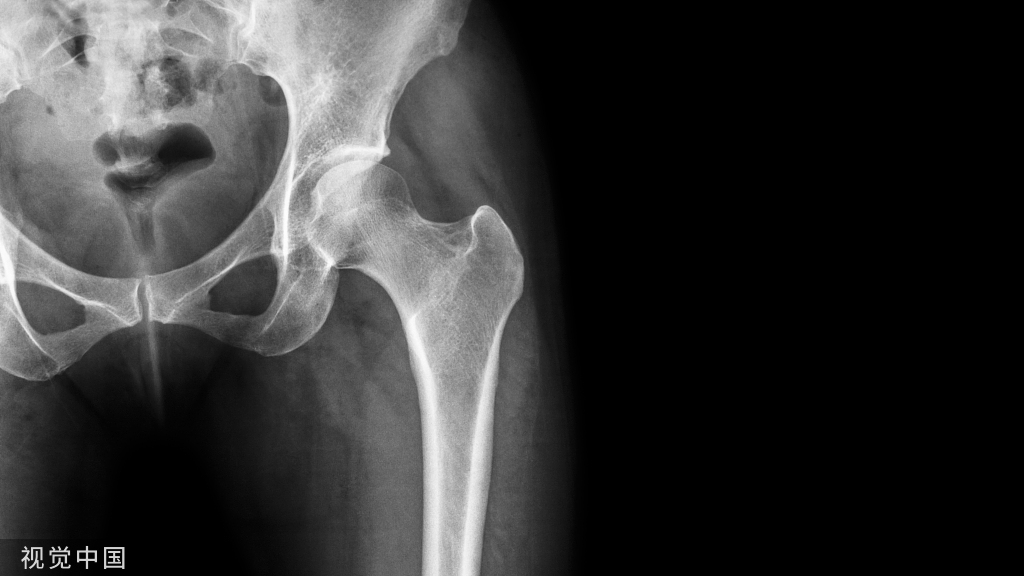

男性,34岁,2019年11月确诊左侧股骨头坏死,2020年1月前来住院行冲击波综合保髋治疗,详情如下:

股骨头内大面积的密度不均减低区就是坏死区。